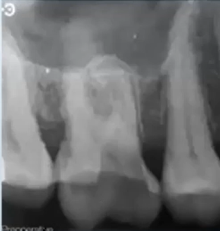

56yo pt had severe toothache for 4 weeks from upper right first molar which suddenly stopped

tooth was asymptomatic on the day he attended, he reported ‘part of the tooth came off recently’ whilst he was chewing

pt smokes 20/day and is a nocturnal bruxist

takes warfarin for atrial fibrilation

BPEs

2 2 2

Large radiolucency – caries

Darkness, shadow that’s the decay/hole in your tooth, gone too far for us to save it as it have reached the nerves inside the tooth

Not sure if be able to restore it as since such a large proportion of it is decayed - empathy

BPE scores – have plaque and calculus in your mouth which can lead to advanced gum disease so need to go through Tx and instructions to help reduce this, smoking will also contribute to this